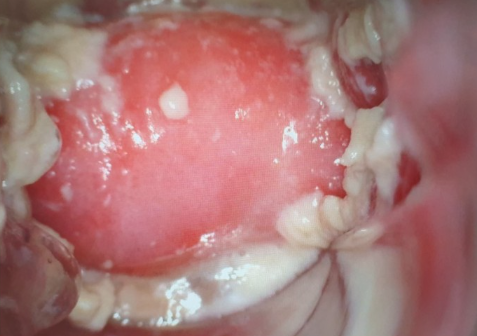

반응성 세포변화란 세포가 염증, 감염, 자극 등의 원인에 반응하여 일시적으로 변형된 상태를 말합니다. 이는 자궁경부세포검사(Pap smear)에서 흔히 나타나는 결과 중 하나이며, 대부분은 양성(비암성)입니다.

자궁경부세포검사에서 발견되는 반응성 세포변화는 자궁경부에 생긴 염증이나 감염, 호르몬 변화 등의 반응으로 세포의 형태나 배치에 약간의 변형이 생겼다는 의미일 뿐, 곧바로 자궁경부암을 의미하는 것은 아닙니다.